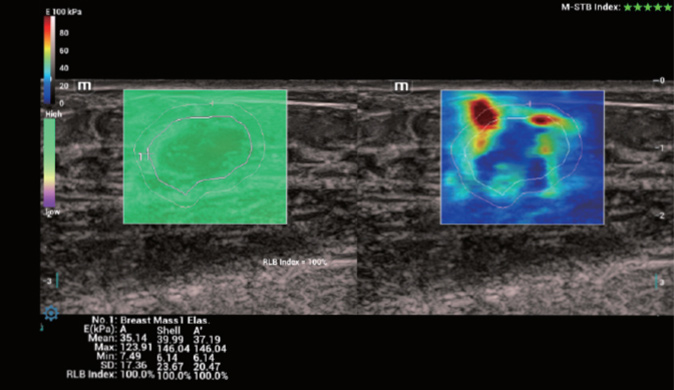

Für die Ultraschalltechnologie stellt die ZST+-Plattform einen bedeutenden Fortschritt dar, da sie statt der herkömmlichen Strahlformung die Kanaldatenverarbeitung verwendet. Diese bahnbrechende Innovation löst übliche Zielkonflikte zwischen räumlicher Auflösung, zeitlicher Auflösung und Homogenität des Gewebes auf, woraus sich eine beispiellose Bildqualität ergibt, die den Weg frei macht für unendlich viele Bildgebungslösungen.

Das Resona I9 weist umfassende klinische Lösungen für spezielle Anwendungen auf. Auf der Grundlage gründlicher Analysen verschiedener klinischer Szenarien liefert es Innovationen, die den Benutzenden herausragende Klarheit, außergewöhnliche Intelligenz und eine erhöhte Diagnosesicherheit bieten.